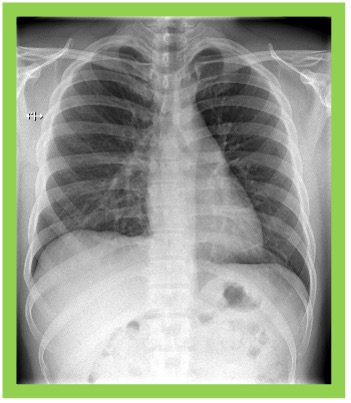

単純X線撮影

胸部や腹部などの体の部位にX線を照射し、透過度の違いを画像化する基本的な検査です。短時間で撮影でき、骨折、肺炎、結核、腸閉塞など様々な病気の初期診断に広く用いられます。体内の構造を視覚的に確認できる重要な検査です。

FPD装置によりコンピュ-タでさまざまな画像処理が可能です。各撮影部位に適した濃度になるように処理されますので、診断能の高い画像を提供することができます。

X線を透過しやすい肺は黒く、透過しにくい骨は白く描出されます。

病巣部は、正常部とX線の透過度が異なるため、正常部とは異なった見え方となります。